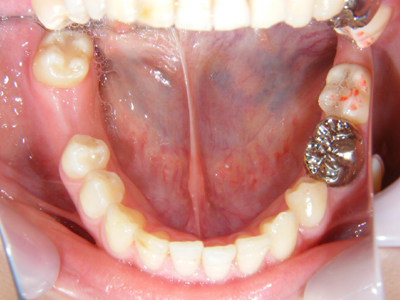

6. 施術前上顎観

上顎左右の8番(移植歯としての利用は断念)、および左上4番の抜歯した後の上顎写真です。これを見て思うのは、1歯レベルではとても良質の歯をしているのに、6番(6歳臼歯)が失活(神経を取った)又はかぶせ物がなされていることから、小学校から高校くらいまでの間は混合歯列期(乳歯と永久歯が共存している時期)や最初に萌出する6番の時期に、歯科的なアプローチが結果的に不十分だったことです。

7. 施術前下顎観

下顎も1歯レベルでは本当に良い歯質をしています。残念なのは右下6番部の欠損(残根は抜歯済み)と、左下に存在する埋伏の5番と6番の関係です。やはり小児期の咬合誘導や口腔保健の対応は重要です。ただ子供の歯の虫歯だけ詰めるのが小児歯科ではありません。(6番は再根治して保健にて冠装着済み)問題は右下で、両隣の天然歯を削ってブリッジにするかどうかです。

8. 施術前右側観

6番部の欠損です。両隣在歯は良い歯をしています。絶対削りたくありません。ましてやブリッジにするために、最後臼歯の咬頭関係を崩してまで削るのは、咬合を崩すことになります。単独インプラント適応です。22歳です。